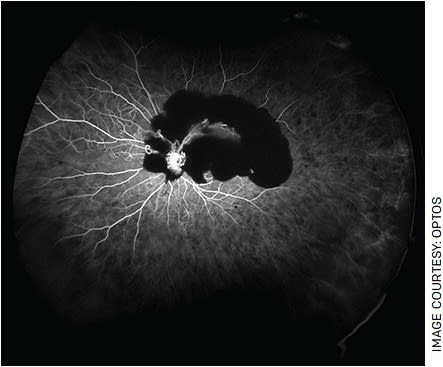

DR is an extremely prevalent cause of visual deterioration, especially in underserved populations. Early detection of its severity can lead to prompt referral and treatment. While standard fundus photography can identify central pathology, including neovascularization of the disc and tractional retinal detachments, Ashraf et al published data in 2021 demonstrating that UWF imaging, especially UWF-FA, is superior in its quantification of ischemic disease secondary to capillary non-perfusion, as well as peripheral signs including pre-retinal hemorrhage and neovascularization elsewhere (NVE) (Figure 1). Both NVE and increased non-perfusion suggest an advanced disease state requiring more aggressive treatment.

FIGURE 1. FA of an eye with advanced diabetic retinopathy